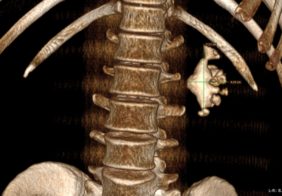

Дроблення коралоподібного каменя через 5 мм. прокол на шкірі

Лікування коралоподібного каменю 1 ступеню право, нирки